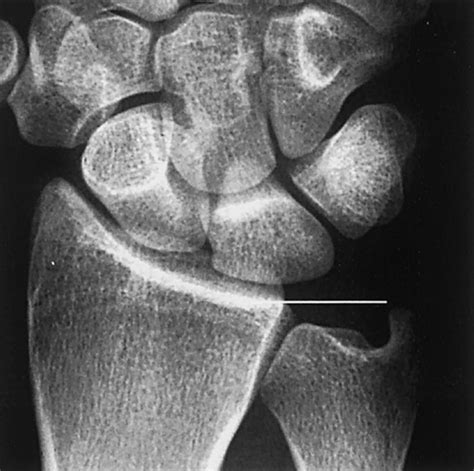

Because of the altered mechanics, this condition is frequently associated with Ulnar Impaction Syndrome. This syndrome describes the actual impingement of the ulna against the triquetrum and lunate (bones in the wrist) and the triangular fibrocartilage complex (TFCC), leading to degeneration of these structures.

Diagnosing Positive Ulnar Variance requires more than a standard physical exam. Physicians typically rely on specific imaging techniques to accurately measure the variance. An X-ray of the wrist is the gold standard for diagnosis. However, how the X-ray is taken matters significantly.

To ensure accuracy, the patient's arm must be positioned correctly. If the arm is not properly aligned, the measurement of the ulnar variance can be falsely positive or negative. The doctor will likely request a posteroanterior (PA) view of the wrist with the forearm in a neutral position. In more complex cases, magnetic resonance imaging (MRI) may be utilized to evaluate the health of the surrounding soft tissues, such as the TFCC and the cartilage of the wrist bones, to see if damage has already occurred due to the impaction.